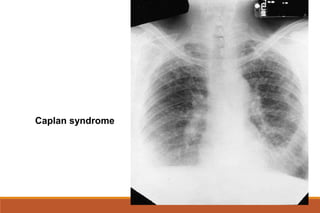

Pulmonary manifestations: pleural involvement, fibrosing alveolitis , obliterative bronchiolitis

Pulmonary rheumatoid nodules

Caplan syndrome